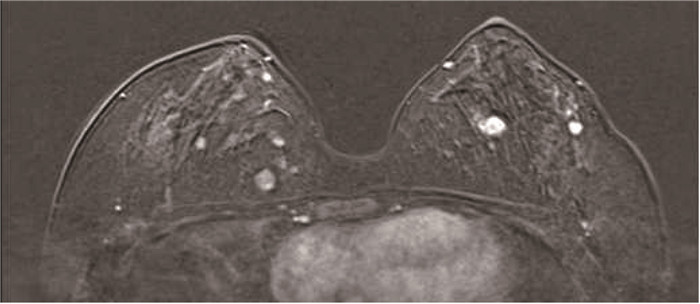

患者乳腺MRI图像